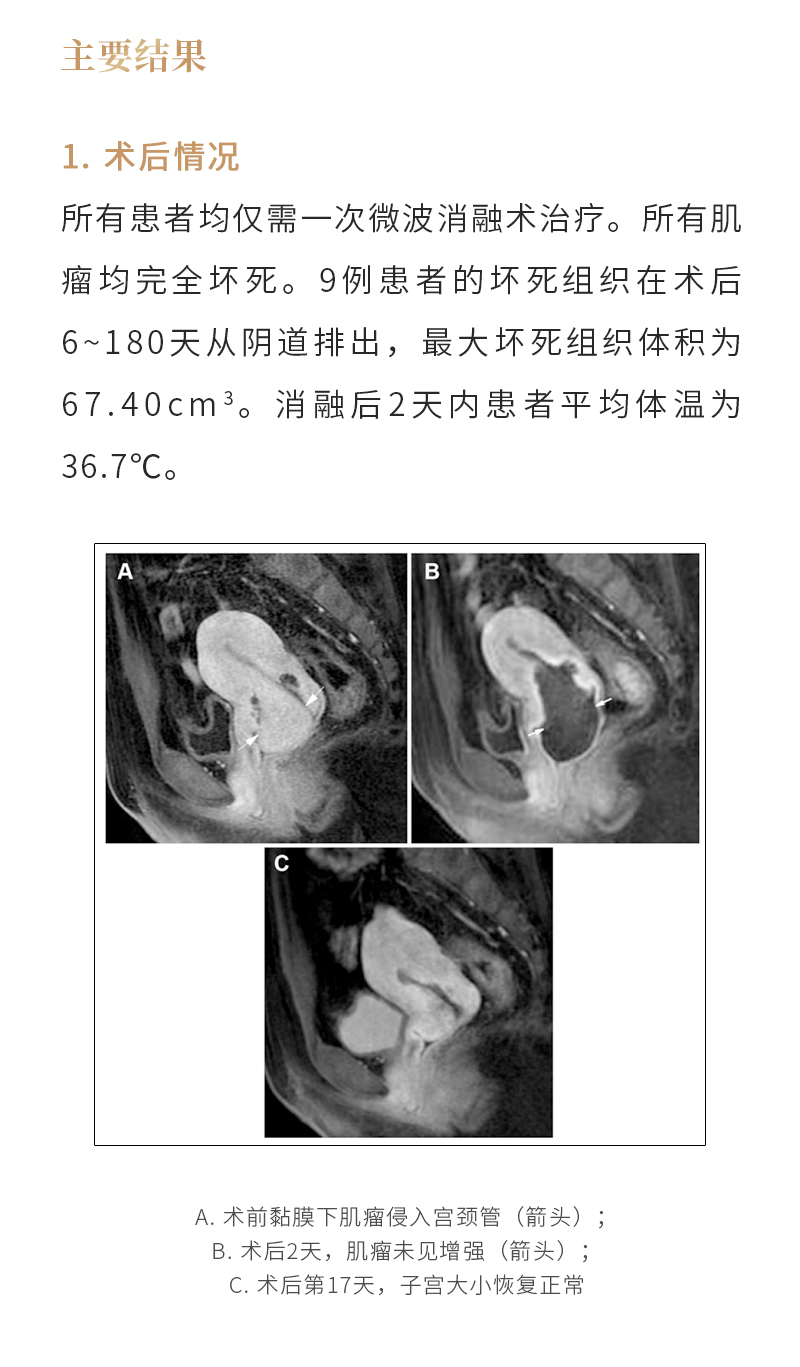

消融治療子宮肌瘤——【海杰亞科研資訊】第260期